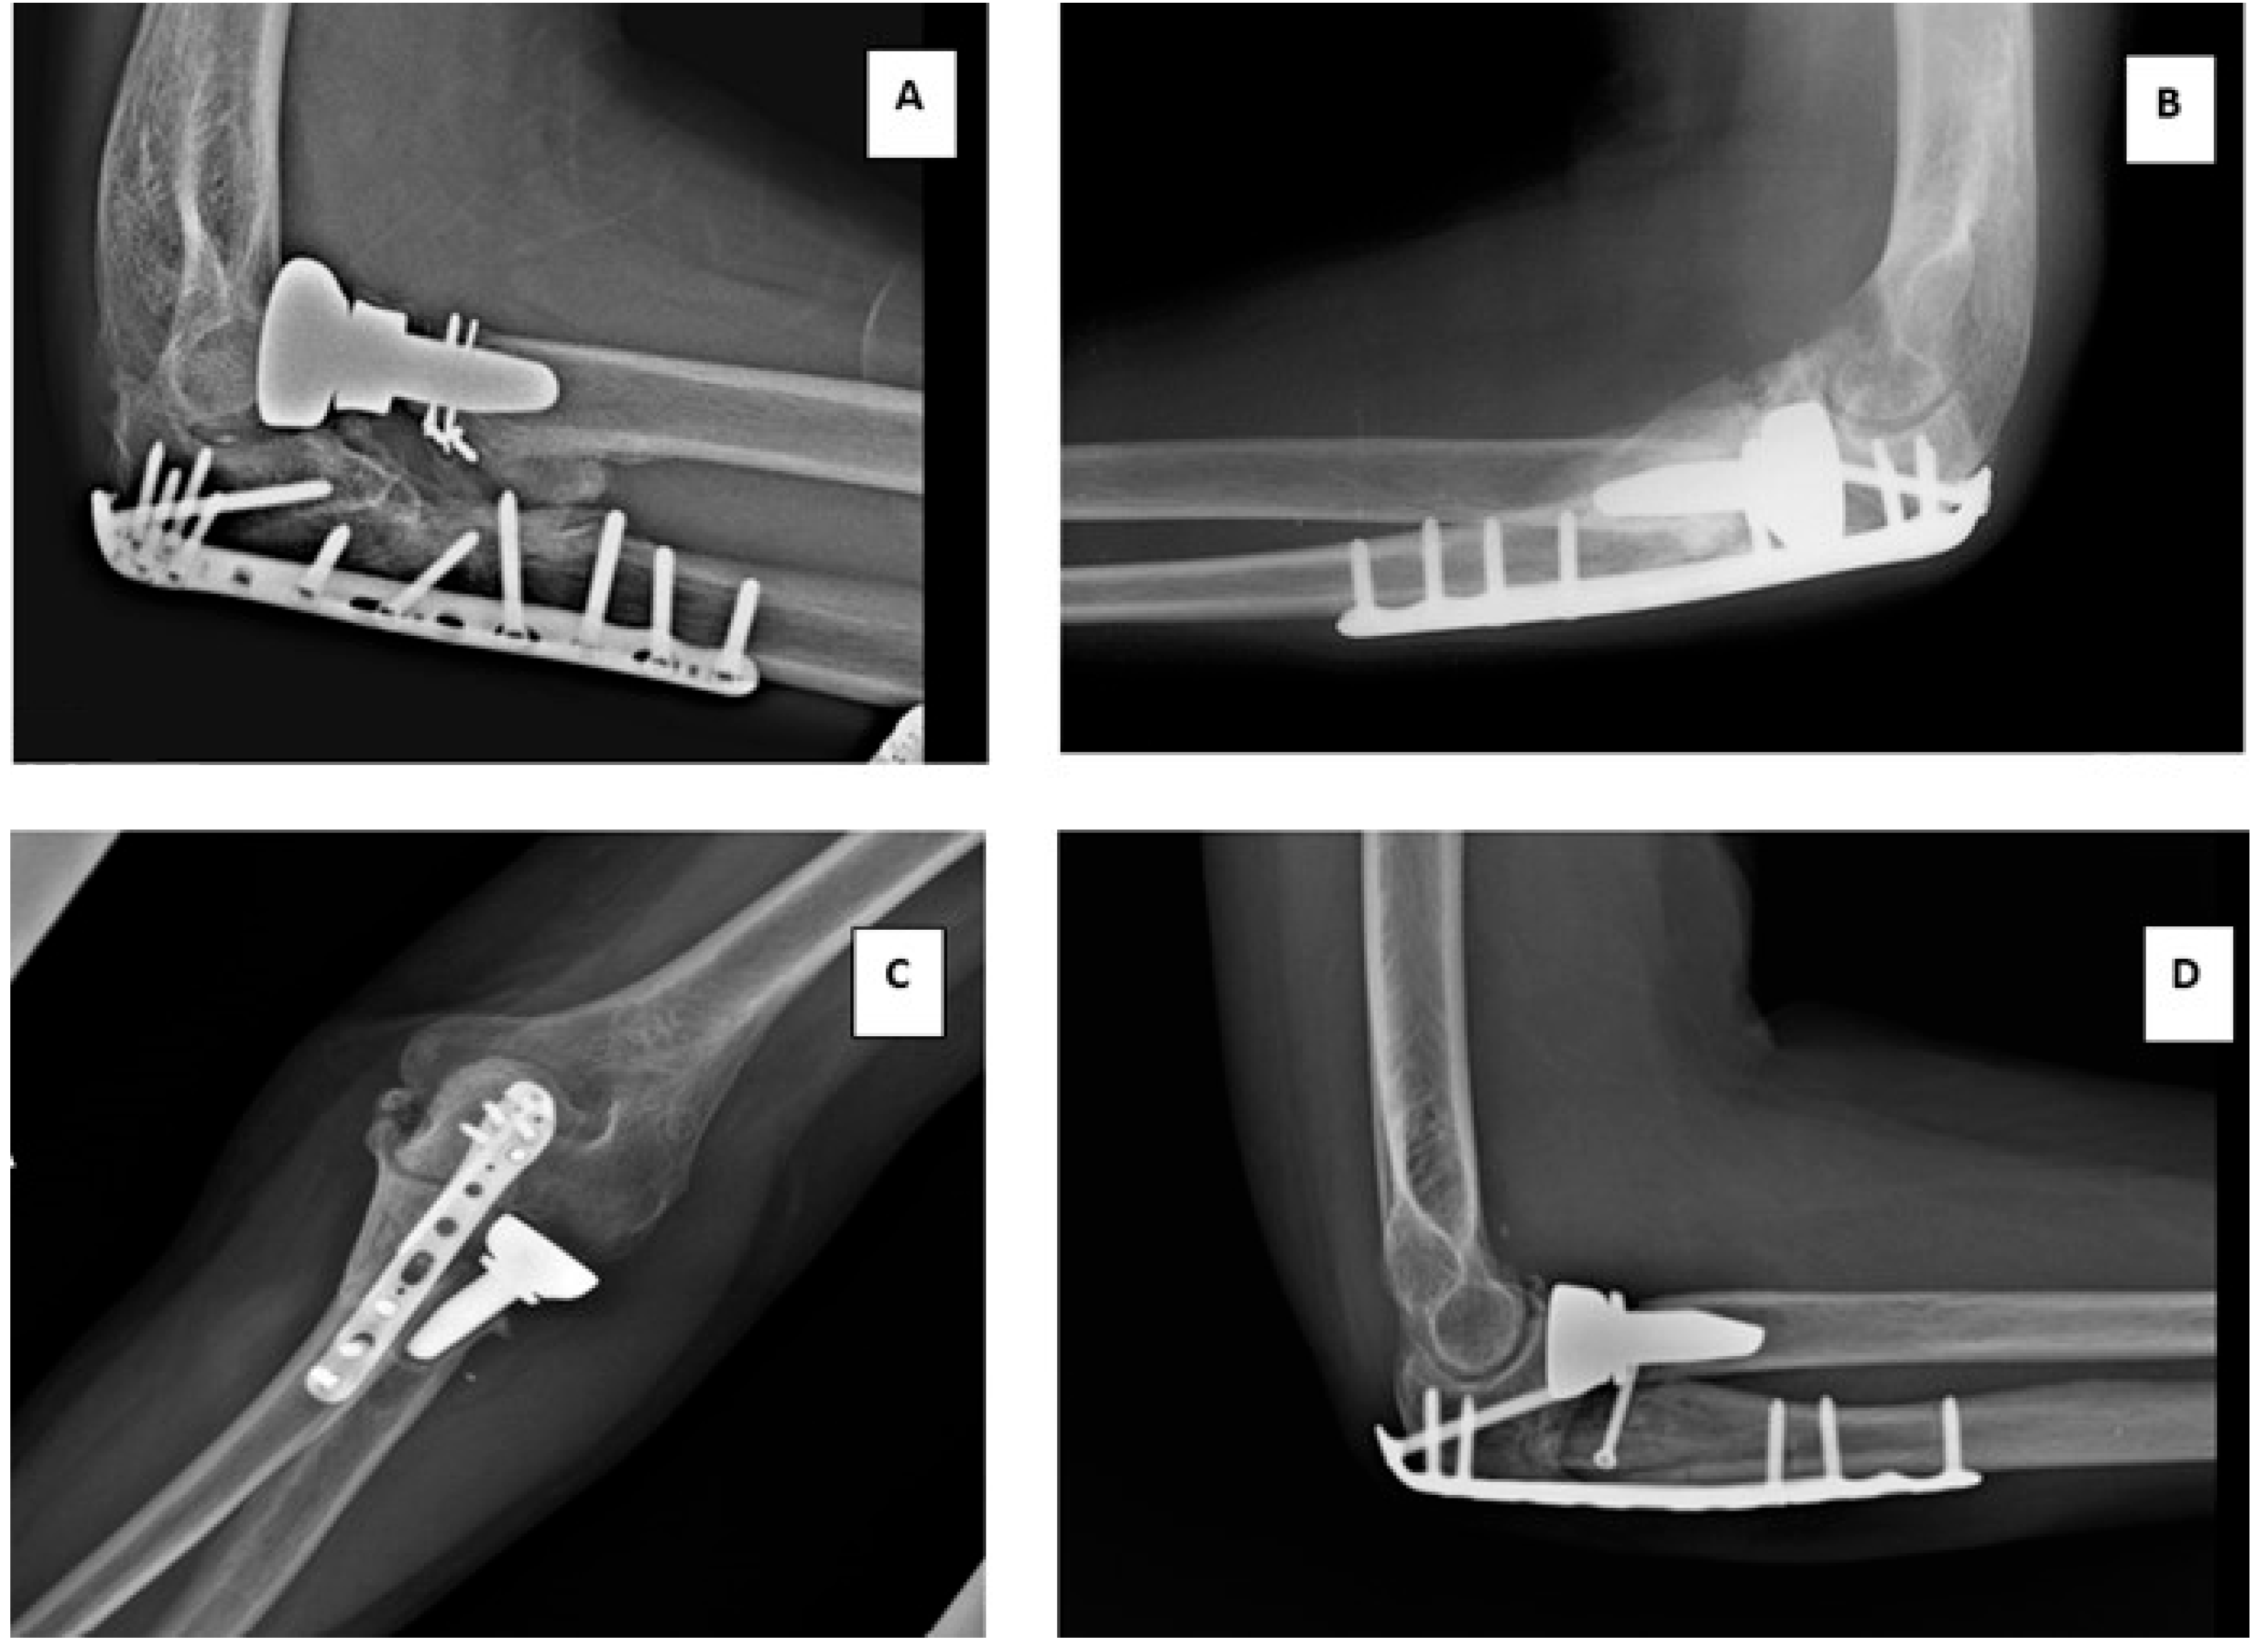

In terms of postoperative radiographic measurement, heterotopic ossification was observed in 17 patients (37.7%), erosion of the capitulum in seven patients (15.5%), osteolysis in 10 patients (22.2%), and loosening of the radial head prosthesis in 2 patients (4.4%) (Table 3). Examples of the radiographic measurements are shown in Figure 6.

Figure 6.

Postoperative X-ray radiographs demonstrating potential complications following RHA. (A) Erosion of the capitulum, (B) heterotopic ossification, (C) loosening, and (D) osteolysis.